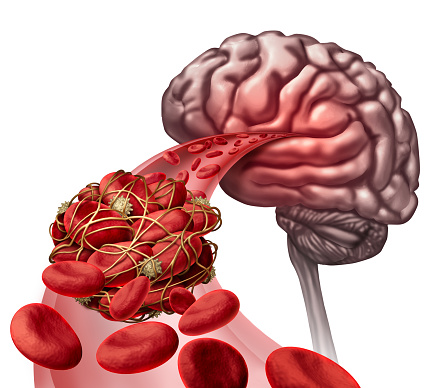

Lacunar infarct, a type of stroke: Causes, symptoms, and treatment options

Lacunar infarct is a type of stroke that occurs when one of the arteries supplying blood to the brain gets blocked. These arteries are quite small, which makes them vulnerable to damage. While most arteries in the body gradually become smaller, the arteries of the lacunar stroke branch off a large high-pressure artery. Lacunar stroke ...click here to read more